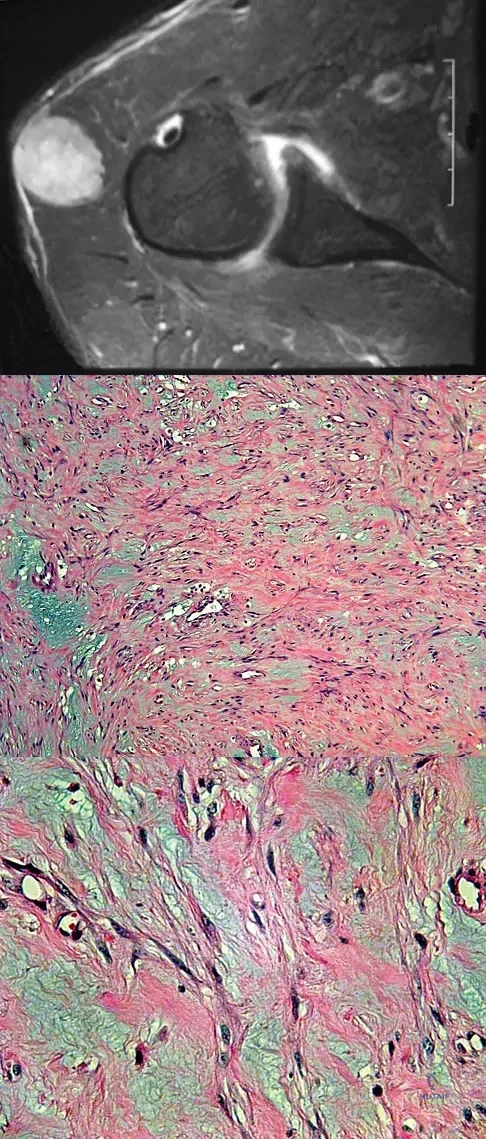

A 40-year-old man reports an enlarging soft-tissue mass in his right shoulder. Based on the MRI scan and biopsy specimens shown in Figures 40a through 40c, what is the most likely diagnosis?

Explanation